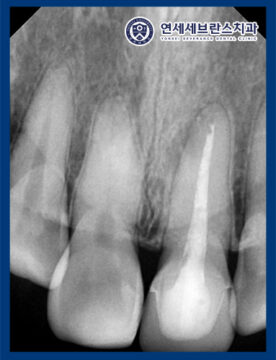

26.01.05 / 26.01.22

<신경치료 진행 및 마무리>

기존에 충전되어 있던 재료와 포스트 제거 후

신경관 내부의 감염 원인을 줄이기 위해

세척과 소독 과정을 꼼꼼하게 진행하였습니다.

보이지 않는 미세한 염증까지 정리하는 것이

재신경치료의 중요한 단계이기 때문에

여러 차례에 걸쳐 신경관 내부를 정리한 뒤

약제를 적용하여 염증 반응이

충분히 가라앉을 수 있도록

경과를 확인하였습니다.

이후 근관 충전을 진행하여

재신경치료를 마무리하였습니다.